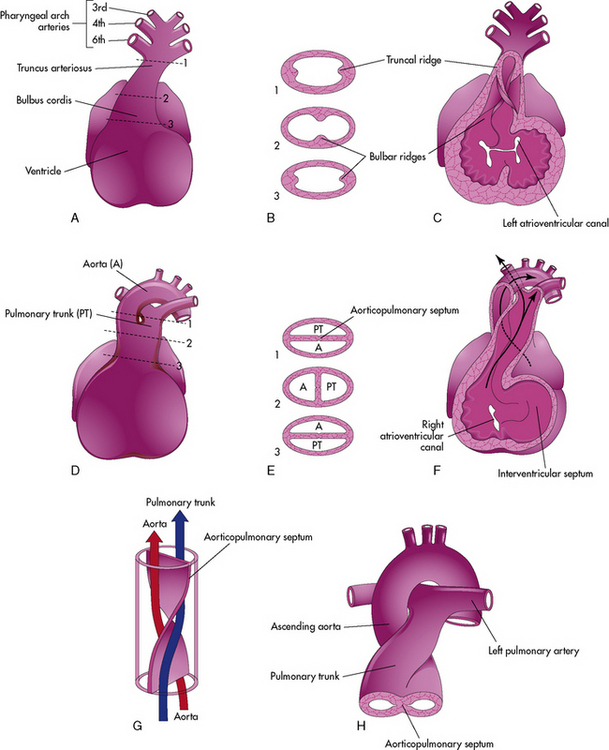

Пороки сердечно-сосудистой системы: виды и признаки